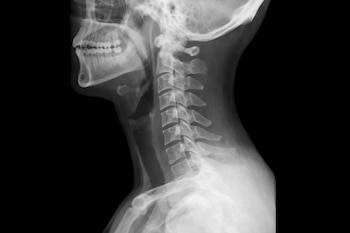

El reciente incidente en Mar del Plata, Argentina, donde un adolescente ingirió accidentalmente un alambre mientras comía galletas, ha puesto de relieve la importancia del diagnóstico por imágenes para detectar objetos extraños en la garganta y otras partes del cuerpo humano.

La presencia de cuerpos extraños en el organismo —ya sea por ingestión accidental, accidentes traumáticos o inserción voluntaria— es una situación común en las salas de emergencias. La clave para un tratamiento exitoso es la localización precisa. Para ello, la medicina se apoya principalmente en dos pilares: la radiografía y la ecografía.

Radiografía convencional (rayos X)

Es la primera línea de defensa. Funciona mediante el uso de radiación electromagnética que atraviesa los tejidos.

Los rayos X atraviesan el cuerpo y son absorbidos en diferentes grados según la densidad de los tejidos, explica Arth Diagnostics.

- Los objetos densos (como el plomo o el hierro) absorben casi toda la radiación y aparecen de color blanco brillante (radiopacos).

- Los tejidos blandos y el aire permiten el paso de los rayos y aparecen en tonos de gris o negro.

¿Qué detecta con precisión?

- Metales: Monedas, clavos, agujas o proyectiles.

- Vidrio: La mayoría de los vidrios modernos contienen plomo o bario, lo que los hace visibles.

- Huesos y piedras: Cálculos o fragmentos óseos extraños.

Limitación principal: Los objetos de baja densidad, como la madera, el plástico fino o la materia vegetal, suelen ser “transparentes” a los rayos X, pasando desapercibidos.